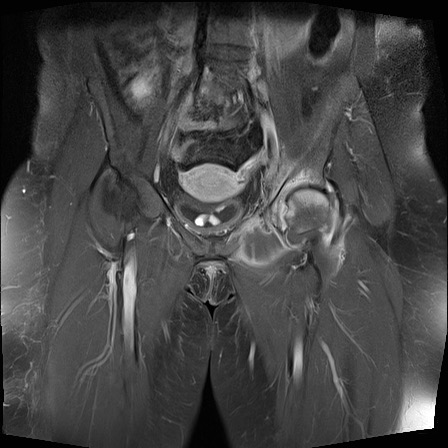

Hình ảnh X-quang khung chậu của bệnh nhân viêm khớp do lao tại khớp háng trái.

Có hẹp khe khớp kín đáo kèm theo xơ cứng dưới sụn tại khớp háng trái.

Các dấu hiệu X-quang này không đặc hiệu và rất có thể là biểu hiện của thoái hóa khớp.

Tiếp tục xem hình ảnh MRI…

Điều bất ngờ với tất cả mọi người là có nhiều ổ áp-xe.

Khi hình thành áp-xe lan rộng như vậy trong khi biểu hiện lâm sàng lại tối thiểu, cần luôn nghĩ đến viêm khớp do lao.

Chẩn đoán viêm khớp do lao được xác lập bằng chọc hút dịch khớp.